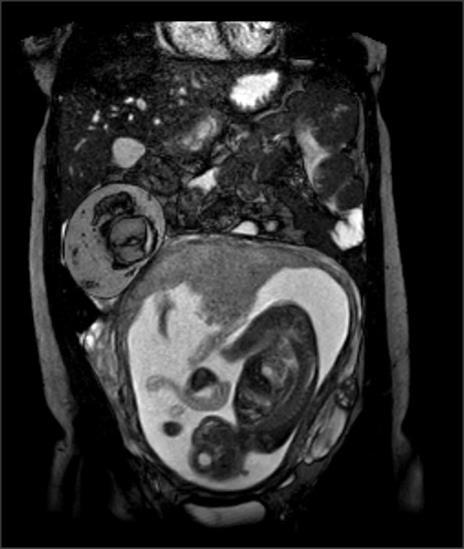

Een 23-jarige vrouw wordt bij een amenorroeduur van 21 3/7 weken door de verloskundige verwezen vanwege acuut ontstane pijn rechts onder in de buik en veelvuldig braken. Zij heeft geen vervoerspijn, bewegingsdrang of vaginaal bloedverlies.